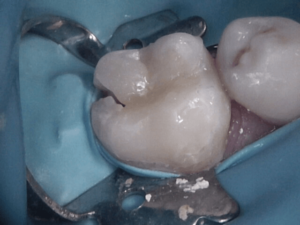

Before and After Treatments

Gordon Street Dental Success Stories in Guelph

Many Patients have allowed us to show what we’ve done for them. Please feel free to look at what we’ve done for them, as well as envision what we can do for you.

Before and After Treatments

Image Grid Title

Read More